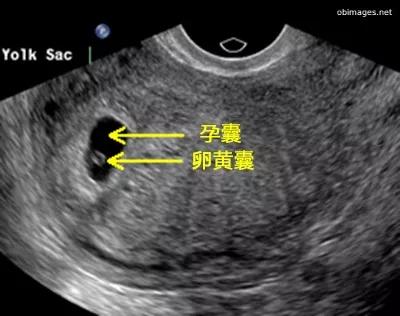

孕囊、胎芽、胎心,这3个是B超专有名词,在孕早期根据时间顺序出现。也就是在子宫内先出现孕囊(确定宫内孕),再出现胎芽(确定孕周),最后出现胎心(提示宝宝存活)。

孕囊

是怀孕最初胚胎的形态,被羊膜、血管网包裹的小胚胎。

孕囊一般只能在孕早期看到。一般情况下,怀孕5周以后,B超可看见小胎囊,胎囊约占宫腔不到1/4,或可见胎芽。在孕11周时,通过B超就可以看到孕囊完全消失,胎盘清晰可见,而孕囊担当的就是一个护宝使者的使命。

孕囊位置在子宫的宫底、前壁、后壁、上部、中部都属正常;形态圆形、椭圆形、清晰为正常;如胎囊为不规则形、模糊,